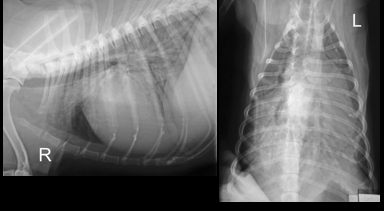

• 13 year old, ME, Cocker Spaniel

• Presented with coughing and retching for several weeks. Recently collapsing.

• Increased respiratory noise on auscultation. RR 38bpm; HR 160bpm, regular. Weak femoral pulses; and pale mucous membranes and CRT > 2 secs.

• DV and lateral

• DV view is rotated which may affect interpretation (care with cardiac silhouette). Cant tell if inspiratory

• Lateral is inspiratory and minimal rotation. Good centre. Collimation etc.

• Cardiac enlargement – large CS. Very tall - Dorsally displaced trachea

• Lung pattern – Alveolar (air Broncho grams, increase opacity, obliteration etc.) caudually. Cr lung lobe has a little increase in opacity but not as affected as much

• Lateral view – lung lobe alveolar pattern and some air bronchograms predominately caudally. Cn see edges of diaphragm, BV and CS. Not all an alveolar pattern as you wouldn’t be able to see these). So there is a part interestital pattern too.

• Bonsell: The whole thorax is affected

• When drawing a line from the trachea bifurcation to the apex there is not an even chamber distribution

• Around 3.5 intercostal spaces width (should be 2.5 -3.5 on lateral)

• Height of the heart on the lateral view is more than 2/3 high at the level of the 5th rib

• Border obliteration of CS on DV and also cant see diaphragm

• Caudal margin is more caudal than it should be and straight – LEFT SIDE ENLARGEMENT

• Not that increased sternal diaphragmatic contact – so right side isn’t enlarged

• No real sign of plural disease

• Hard to assess vessels due to patterns